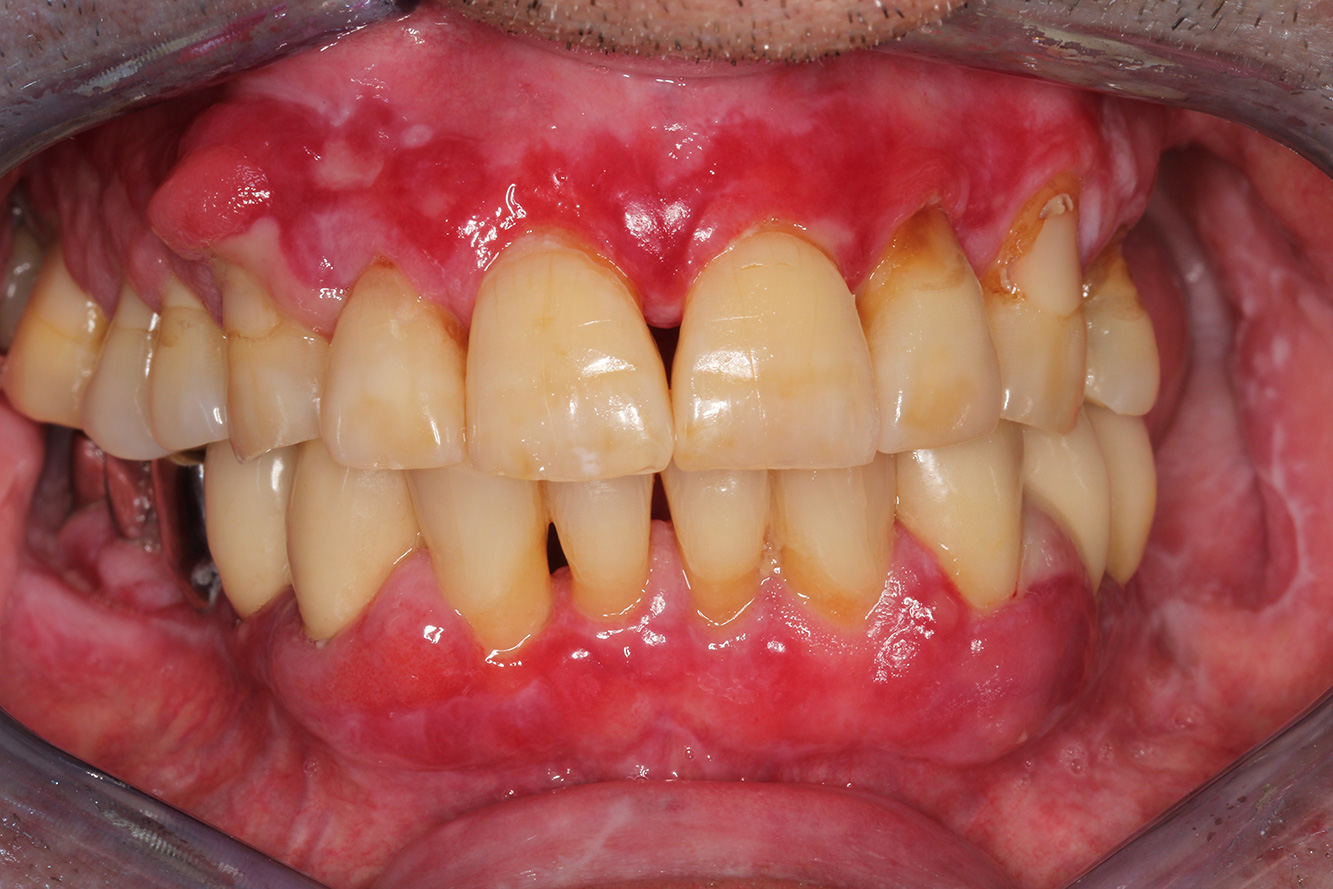

In the medical history, the 55-year-old patient states that he has no systemic disease and is not taking any medication. The patient’s lifestyle is similarly unremarkable. The patient has a few tooth restorations and two implants (2nd and 4th quadrants). On the basis of current findings, gingivitis is identified in an otherwise stable periodontal condition on the reduced periodontium (stage III, grade A). more

The healthy patient with pre-existing periodontal disease & peri-implantitis

Un pacient în vârstă de 71 de ani, cu transplant de rinichi și istoric de hipertonie (hipertensiune arterială) se prezintă în cabinet. Din cauza istoricului său medical, este necesară o medicație pe termen lung cu ciclosporină, pentru a suprima sistemul imunitar, precum și amlodipină pentru a reduce tensiunea arterială. Pacientul raportează, de asemenea, gingii sensibile și sângerânde. Din punct de vedere al sănătății orale, pacientul are lucrări dentare, o edentație de opt dinți, creștere gingivală pronunțată și parodontoză de gradul B, stadiul II, cu pungi active și carii radiculare inițiale la dintele 22. Evaluarea riscului de carie determină un risc moderat de carie (API 60). Se pot stabili următoarele recomandări de tratament pentru ședința de profilaxie. mai multe

Pacientul în vârstă de 68 de ani nu are nicio afecțiune generală și nu ia niciun medicament care ar putea fi relevant pentru sănătatea sa orală, iar stilul său de viață nu prezintă niciun risc special. Pacientul are două implanturi dentare (cadranul 3, de cinci ani) și un caz anterior de boală parodontală (stadiul IV, gradul B) cu pierderea dinților. În prezent, condițiile parodontale sunt stabile. Cu toate acestea, parodontoza crește semnificativ complicațiile biologice ale implanturilor și există riscul de pierdere a implanturilor (21). Se pot determina patru recomandări pentru ședința de profilaxie. mai multe